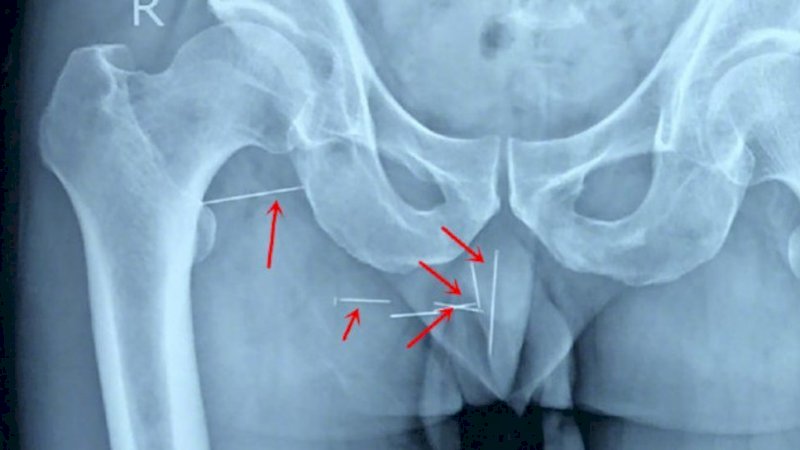

Awal bulan ini, ia akhirnya memutuskan untuk pergi berobat dan melakukan X-ray. Setelah itu dia menemukan penyebabnya: delapan jarum bordir, dikutip dari Shanghaiist, Sabtu (24/8/2019).

Chen secara tidak sengaja jatuh saat mengerjakan tumpukan memo, termasuk sekantong jarum yang kemudian bersarang di pantatnya. Chen menarik mereka sendiri dan percaya bahwa dia telah melepaskan semuanya.

Ternyata tidak, beberapa dari jarum itu telah tinggal bersamanya selama 10 tahun terakhir, menjadi sumber ketidaknyamanan dan rasa sakit.

Jarum itu akhirnya dikeluarkan lewat operasi empat jam di rumah sakit.